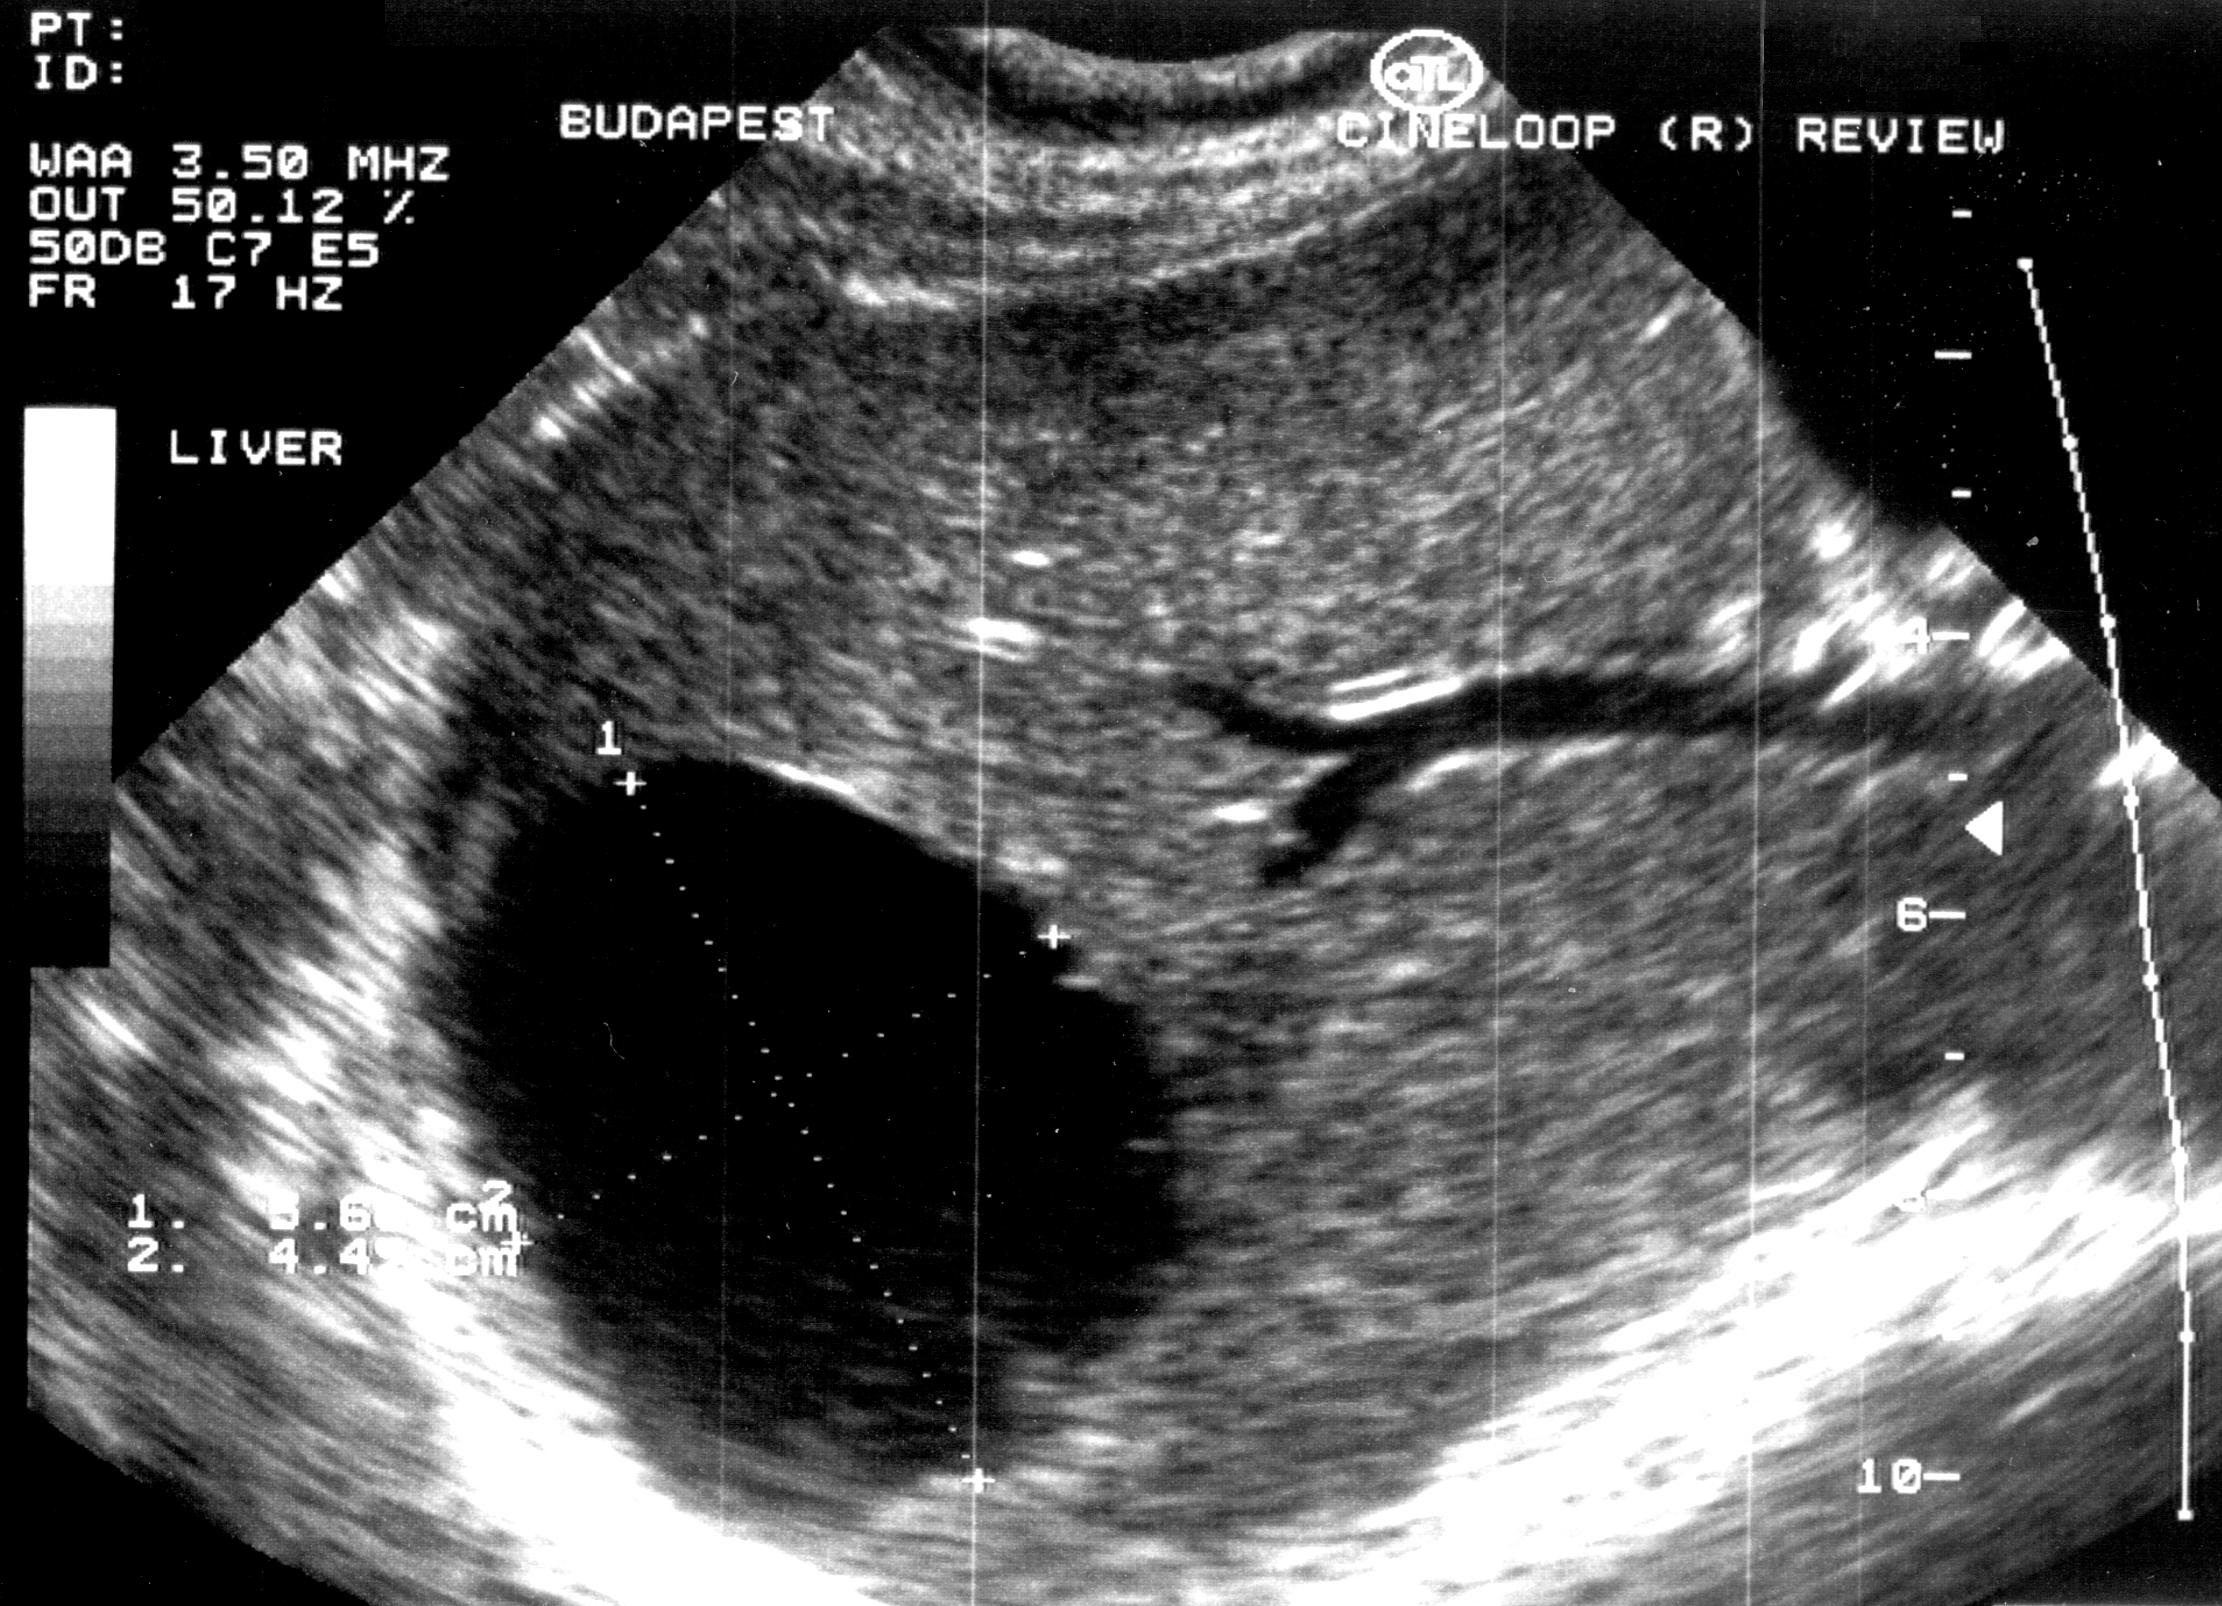

Abscess healing can be accelerated by repeated drainage and lavage of the contents of the abscess. (Figure 11.)

Image

Figure 10. – Hepatic cyst before alcoholic sclerotization, cyst is filled with diluted contrast material.

Figure 11. – US guided hepatic abscess drainage control (day 13, after several rounds of lavage and cleaning of the abscess)

The length of the percutaneous drainage is influenced by the washout of the contents and the reduction of its size.